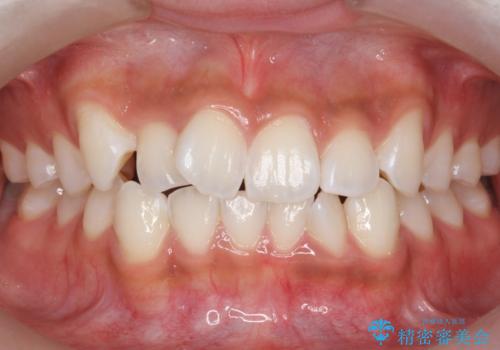

出っ歯と歯のねじれ 非抜歯で 30代男性

- 前歯の並びを気にして来院。

奥歯のかみ合わせを特に変えず、前歯の並びを整える治療をおこないました。

右上のかみ合わせをそのままにするため、上下の正中は合わない仕上がりとなります。

右のかみ合わせを変えず部分矯正にしたことによって、治療が短期間で済み、また、ワイヤーでなくインビザラインで治療が可能、歯も抜かなくて済むなどメリットの多い方法であるといえます。